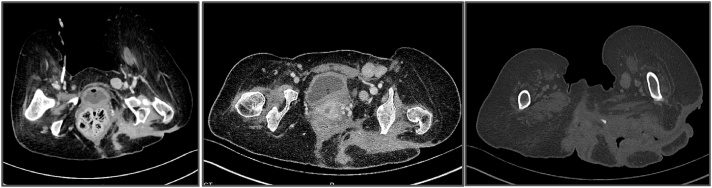

Fig. 2.

a–c: CT scan showed multiple burrows and enlarged lymph nodes.

One year later, the lesion reappeared, and the clinical signs were highly suspicious for malignancy (see Fig. 4). A biopsy of the lesion was performed, and the histopathologic results confirmed our suspicion of a well-differentiated squamous cell carcinoma. A subsequent CT scan revealed focal calcification within the large primary lesion and an additional axillary mass (3.9 cm) with a necrotic lymph node; there was no additional lymphadenopathy (see Fig. 5 a and b). Four other cysts (7.2 cm) in the anterior thorax wall were also observed.

Fig. 5.

a and b: The CT scan revealed focal calcification within the large lesion, an additional axillary mass (3.9 cm) with a necrotic lymph node and no additional lymphadenopathy. Four other cysts (7.2 cm) in the anterior thorax wall were also observed.